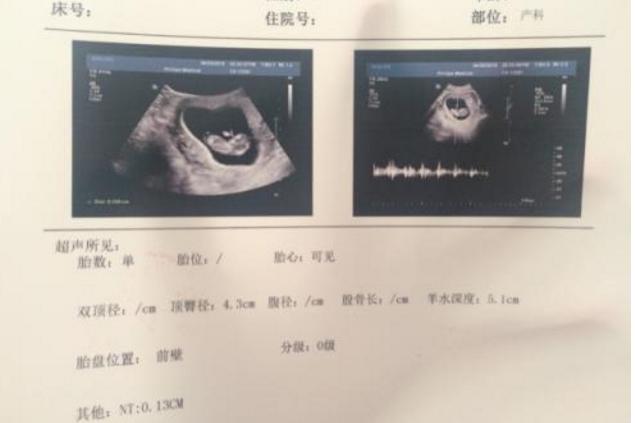

其实NT检查的目的跟唐筛的目的是一样的都是,都是用来检测胎儿是否用唐氏综合症的!一般来说在孕期10~14周的时候做的!这个检查是通过超声波扫描来做的,而且还分为两种一种是照肚子,一种是需要通过阴道!这两者的差别估计很多孕妈都知道,阴道B超确实要比肚子的B超更加清楚!只是会略带羞耻而已!

我们都知道唐氏筛查的时间是15~18周的时候做的,而NT检查是10~14周的时候做的,虽然都是用来检测胎儿是否有唐氏综合症,但用途有点重复,而且时间间距很小,自然很多孕妈都选择忽略这个检查!其实在启蒙小哥看来,不管你是做NT还是唐筛两个做了一个就可以了!没有必要两个都做!做NT也可以,做唐筛也可以!效果都是一样的!只不过做NT会更早的知道胎儿是否健康而已!